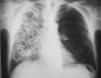

Se interpretó el cuadro como neumonía, posiblemente en relación con broncoaspiración inadvertida, y se trató con amoxicilina-ácido clavulánico (2g/8h, vía intravenosa). La evolución clínica fue favorable, pues mejoraron tanto el estado general como los síntomas respiratorios, la insuficiencia respiratoria y la alteración de las pruebas hepáticas. En la radiografía se observó una ligera mejoría. Se dio de alta al paciente con tratamiento antibiótico. Cuando acudió a revisión un mes después, presentaba un claro deterioro general, con pérdida de 4kg de peso, y refería expectoración abundante, purulenta y hemoptoica, pero no fiebre. En la radiografía de tórax se apreciaba un empeoramiento notable, con aparición de varias cavitaciones en el pulmón derecho y pérdida de volumen de éste (fig. 1). La TC torácica evidenciaba un patrón alveolar con cavitaciones que afectaban a los 3 lóbulos del pulmón derecho y a la língula (fig. 2). La serología para el virus de la inmunodeficiencia humana fue negativa en 2 determinaciones. Las baciloscopias y la técnica de reacción en cadena de la polimerasa para Mycobacterium tuberculosis en esputo fueron repetidamente negativas, así como los cultivos de micobacterias. La serología por inmunodifusión de inmunoglobulina G para H. capsulatum, Coccidioides immitis, Blastomyces dermatitidis y Paracoccidioides brasiliensis fue negativa. La broncoscopia no mostró alteraciones endobronquiales. Se tomaron muestras mediante catéter telescopado, lavado broncoalveolar y broncoaspirado, con resultados negativos para bacterias aerobias y anaerobias, así como para micobacterias. Finalmente en todas las muestras de broncoscopia, así como en la de punción transtorácica (realizada tras los resultados inicialmente negativos de la broncoscopia), se observó el crecimiento de un hongo dimórfico identificado unas semanas después, en el Centro Nacional de Microbiología de Majadahonda, como H. capsulatum.